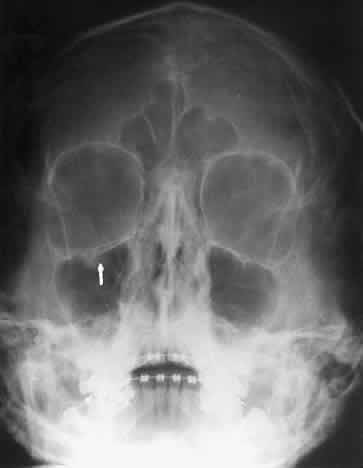

Calcification in the orbit can be seen in retinoblastoma, meningioma, organized hematoma, or a phlebolith associated with venous malformations. Intraocular calcification is seen with tumors such as retinoblastoma or with degenerative changes of the lens, choroid, or vitreous23 (Figs. 10 and 11).

Fig. 10. Caldwell projection of a hemangioma of the left orbit. Soft tissue density is seen in the lateral orbit with partial calcification (arrows).

Fig. 11. A phthisis bulbi globe with calcification of the choroid and sclera. Note the outline of the globe and the location within the orbit. Calcification of the globe can occur with degenerative changes of the eye.